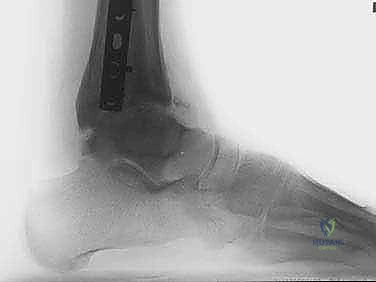

- الأشعة السينية (X-rays) مع الوقوف: لتقييم المسافة المتبقية من المفصل وتحديد درجة الخشونة ومحور الساق.

- الأشعة المقطعية (CT Scan): للحصول على صورة ثلاثية الأبعاد للعظام، واكتشاف أي تكيسات عظمية (Bone cysts) أو نتوءات عظمية (Osteophytes).

يتم تمرير أسلاك معدنية رفيعة جداً (Kirschner wires) ومسامير نصفية (Half-pins) عبر العظام لتثبيت الحلقات. يعتمد الأستاذ الدكتور محمد هطيف على معرفته التشريحية العميقة واستخدام جهاز الأشعة المرئي (C-arm) لضمان مرور هذه الأسلاك في "الممرات الآمنة" (Safe corridors) بعيداً عن الشرايين والأعصاب الحيوية.

هنا يكمن السر الأكبر للنجاح. يتم توصيل حلقة الساق بحلقة القدم باستخدام مفاصل معدنية قابلة للحركة (Hinges). يجب أن يتم وضع محور هذه المفاصل المعدنية ليتطابق تماماً مع المحور التشريحي الطبيعي لدوران مفصل الكاحل (Center of Rotation of the Talus). هذه الدقة تضمن إمكانية تحريك الكاحل أثناء فترة العلاج دون إحداث ضغط غير متساوٍ على الغضروف.

أثناء العملية، يقوم الدكتور هطيف بإبعاد حلقة الساق عن حلقة القدم تدريجياً وببطء باستخدام قضبان ملولبة، حتى يصل إلى مسافة تشتيت تبلغ حوالي 5 إلى 6 ملليمترات. يتم التأكد من هذه المسافة عبر الأشعة السينية داخل غرفة العمليات.